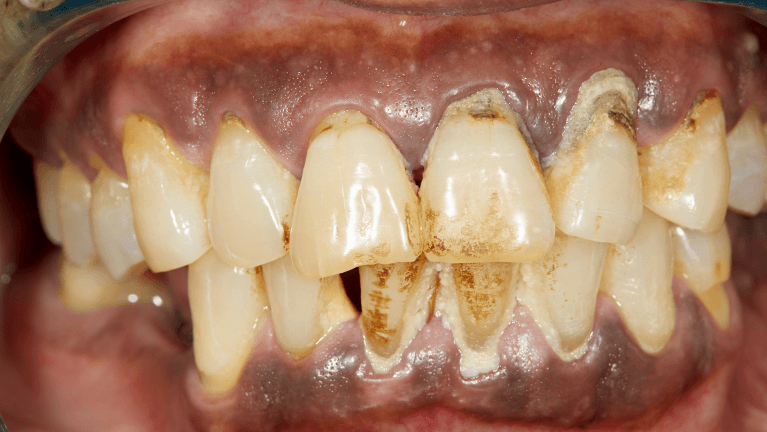

As the infection advances, symptoms become more noticeable. Periodontal disease may cause:

- Gums pulling away from the teeth (recession), creating "pockets" where bacteria thrive

- Visible pus between the teeth and gums

In advanced stages, untreated periodontal disease can lead to bone loss in the jaw, causing irreversible damage.